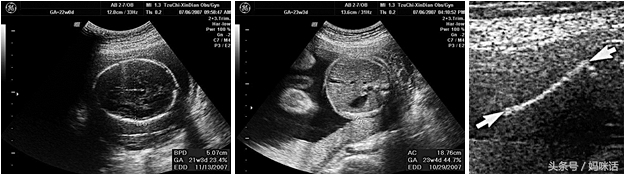

右边前三张各是头径(biparietal diameter, BPD)、腹围(abdominal circumference, AC)与大腿骨长度(femoral length, FL)。这是怀孕五个月后最常听到的「三围」。由以上的数值,可以推算胎儿的体重。因此,中后期胎儿的发育正不正常,可以从这三个数值来判断。